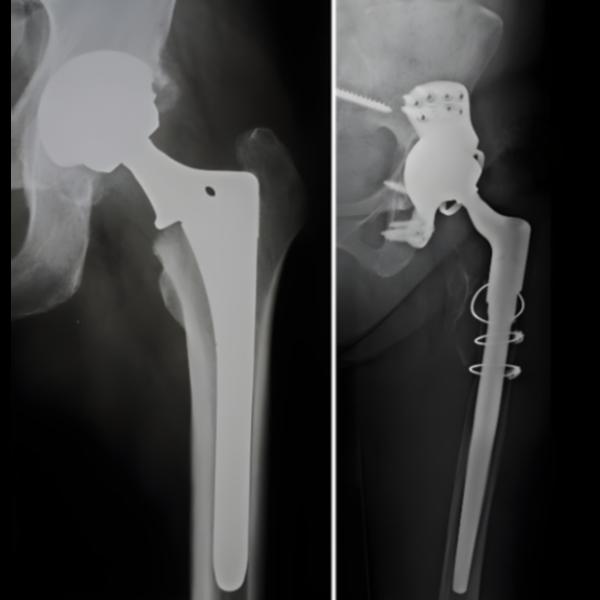

Revision Hip Replacement in Bangalore – Restoring Function and Comfort